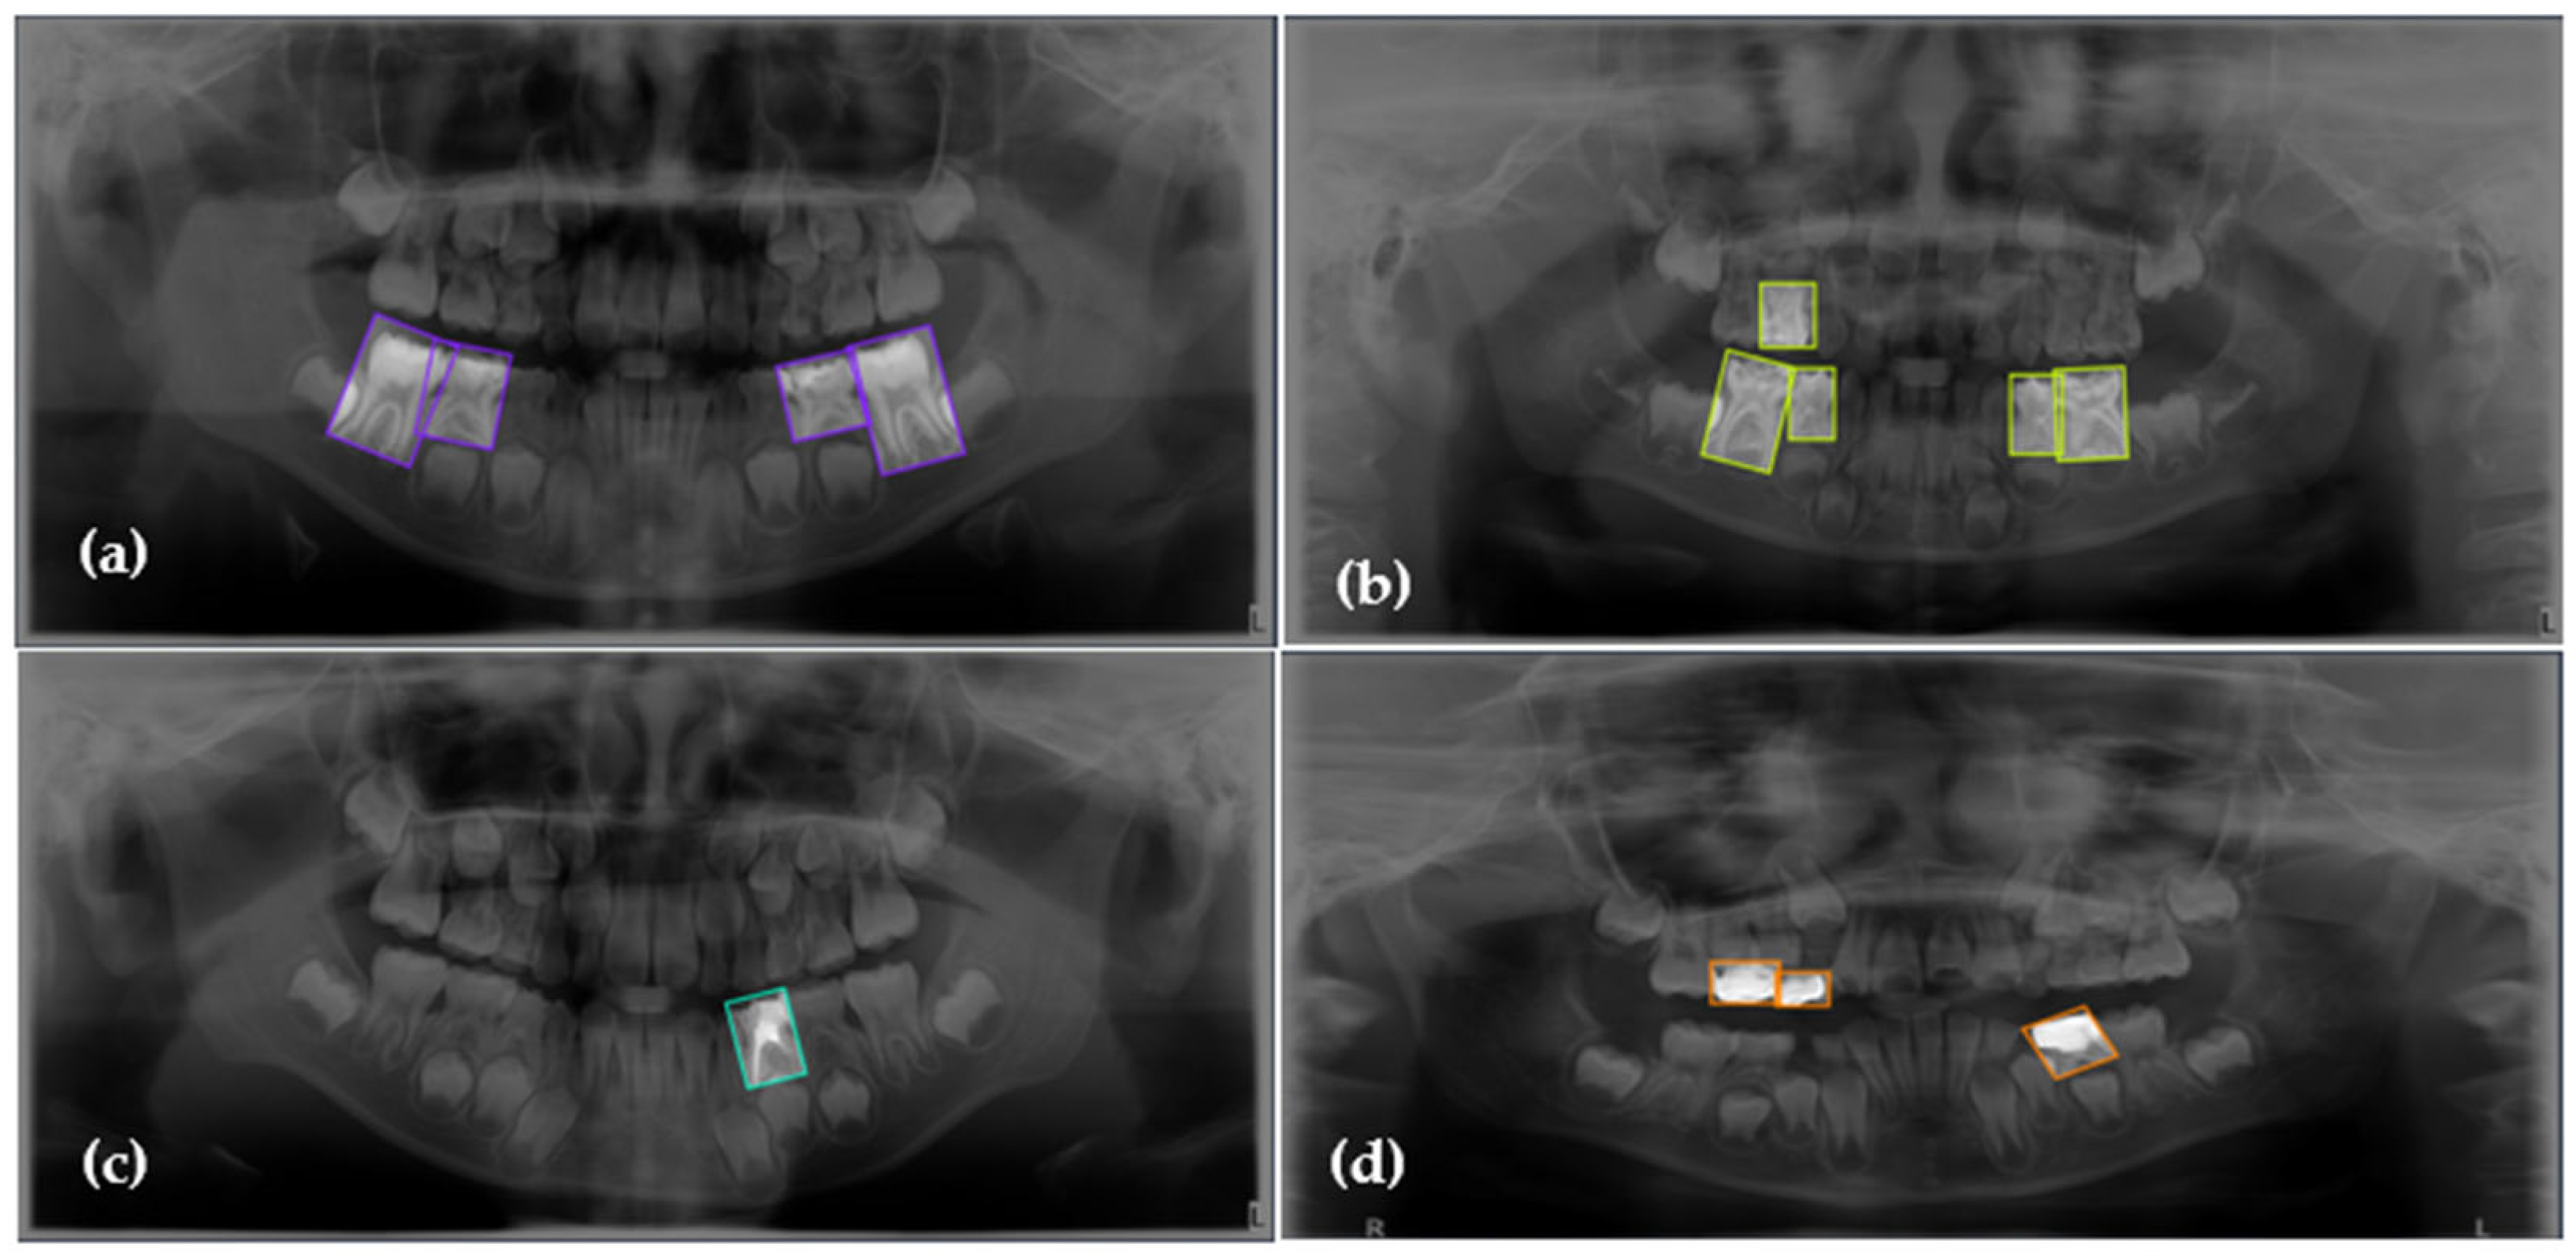

| Dental Caries | 830 | 43.57 | 43.57 |

| Deciduous Tooth | 791 | 41.52 | 85.09 |

| Root Canal Treatment | 171 | 8.98 | 94.07 |

| Pulpotomy | 113 | 5.93 | 100.00 |